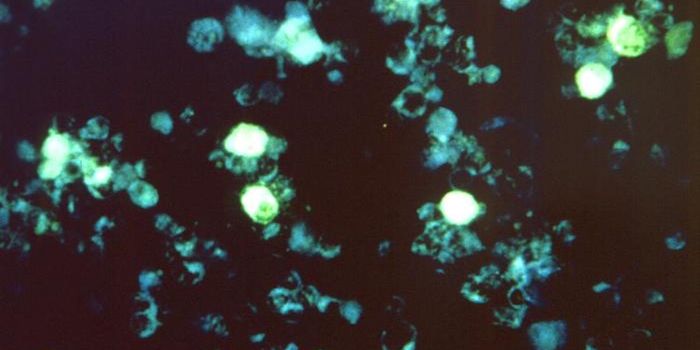

MAY 02, 2024CancerWe interact with small, single-cell organisms on a regular basis. These tiny cells, known as bacteria, represent a ...